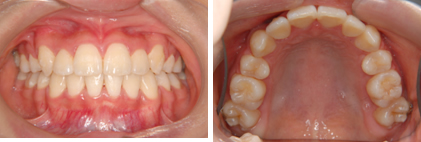

4.大人の治療 (全体的な治療)

全体的な治療 20歳

治療前(抜歯あり)

治療後

※この治療には個人差があります

①主訴:全体的な歯の不揃いを治したい

②診断名あるいは主な症状:叢生

③年齢:20歳

④治療に用いた主な装置:マルチブラケット装置

⑤抜歯部位:上下第1小臼歯を4本抜歯

⑥治療期間:2年半

⑦治療費:検査:49,500円

基本矯正費用:880,000円~

調整料:6,600円(ひと月に1回)

⑧リスクと副作用:治療開始後数日は噛むときに痛みがあります。

虫歯や歯肉炎予防のために毎日の適切な歯磨きが重要。

装置が破損する場合があり、その時は連絡が必要

治療後には後戻り防止として保定装置が必要

歯の移動により歯根の先が溶ける場合がまれにある。